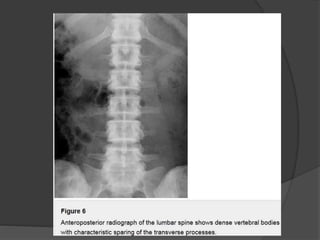

Dense vertebral bodies with characteristic sparing of the transverse

processes is seen.

Pyknodysostosis Patients with pyknodysostosispresent with a complex of characteristic features, including • dwarfism • pectus excavatum • short fingers from acro-osteolysis • hypoplasia of the facial bones, causing dysmorphic facial features. Radiographically, there is generalized osteosclerosis similar to osteopetrosis, but with preservation of the medullary canal of long bones. Dense vertebral bodies with characteristic sparing of the transverse processes is seen.